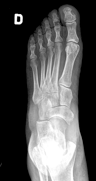

POSICION 1 : PIE AP (DORSOPLANTAR)

Paciente en decubito supino,la rodilla flexionada y con la planta del pie sobre el cassete radiografico.El haz de rayos se dirige verticalmente a la base del primer metatarsiano.

CONSIDERACIONES MEDICAS Posicion 1 : PIE AP

Radiografía en la que se debe tomar en cuenta la totalidad de los elementos, los óseos así como las partes blandas , por lo que es importante recalcar que sean observados , parte del tarso los metatarsianos y sobre todo la orientación de falanges, no es imprescindible el desplegar los sesamoideos ya que estos serán mejor apreciados en enfoques oblicuos y perfiles .También en este enfoque es importante apreciar la congruencia articular del tarso y de los metatarsianos con las falanges , la mesura de los ángulos interdigitales y de las falanges entre si son muy importantes en ortopedia.

Nota jamás conformarse con solo este enfoque , siempre deberá estar acompañado de un perfil , y si es necesario una oblicua . Dr.Aramayo